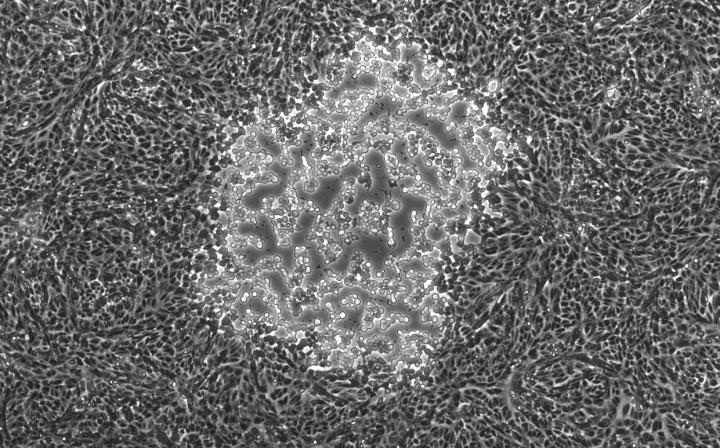

This image shows a focal point of infection by the herpes simplex virus type 1 (HSV-1) from one of the strains sequenced in research led by Moriah L. Szpara at Penn State University.

Penn State University